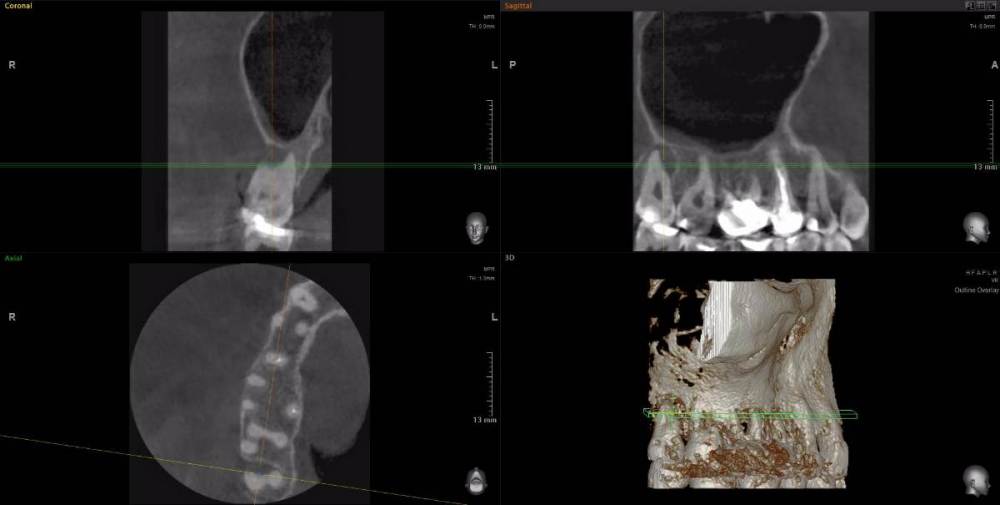

Рабин Опубликовано 18 мая, 2021 Автор Поделиться Опубликовано 18 мая, 2021 Добрый день! Сделала КТ этого зуба, как вы просили... https://cloud.mail.ru/stock/kkbze24nzBzfEqnUbdPwtsei Видите ли вы воспаление на нём и можно ли его спасти? Интересует также соседний 15 зуб. Спасибо! Ссылка на комментарий

wladdX Опубликовано 18 мая, 2021 Поделиться Опубликовано 18 мая, 2021 (изменено) Зуб 16, на мой взгляд, придётся удалить. Зуб 18 тоже Зуб 15 вроде бы и не вызывает особых восторгов, но и явного неприятия тоже. Изменено 18 мая, 2021 пользователем wladdX 2 Ссылка на комментарий

red_butler Опубликовано 20 мая, 2021 Поделиться Опубликовано 20 мая, 2021 18.05.2021 в 23:24, wladdX сказал: Зуб 16, на мой взгляд, придётся удалить. +1 Ссылка на комментарий

wladdX Опубликовано 29 мая, 2021 Поделиться Опубликовано 29 мая, 2021 18 - там приличных размеров корневая гранулёма, излечить нереально 1 Ссылка на комментарий